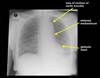

Imaging

CXR: ARDS, exclude perforated DU

AXR: sentinel loop, pancreatic calcification